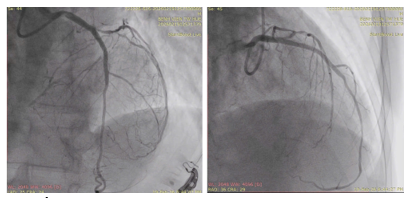

Hình 3: Kết quả sau can thiệp LAD với Stent tại vị trí đoạn thân chung và LAD đoạn đầu.

Sau khi can thiệp cấp cứu LAD, bệnh nhân được tiến hành can thiệp trì hoãn tiếp theo nhánh RCA dưới sự hướng dẫn của siêu âm nội mạch (IVUS) (hình 4 và hình 5). Bệnh nhân sau đó ổn định và ra viện sau một tuần điều trị.

Hình 4. Kết quả sau can thiệp RCA với stent từ DI đến đoạn DIII.

Hình 5. Hình ảnh IVUS sau can thiệp với kết quả Stent nở tốt, áp sát thành mạch với diện tích lòng mạch lần lượt là 5,13 mm2, 8,49mm2; 8.97 mm2; 10,65 mm2 từ đoạn xa đến đoạn gần.